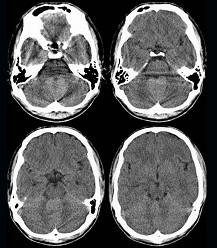

问题 男,16岁,头痛、呕吐10天,CT检查如图所示,最可能的诊断为()

选项 A.脑膜瘤 B.髓母细胞瘤 C.室管膜瘤 D.脑血管瘤 E.血管母细胞瘤

答案 B